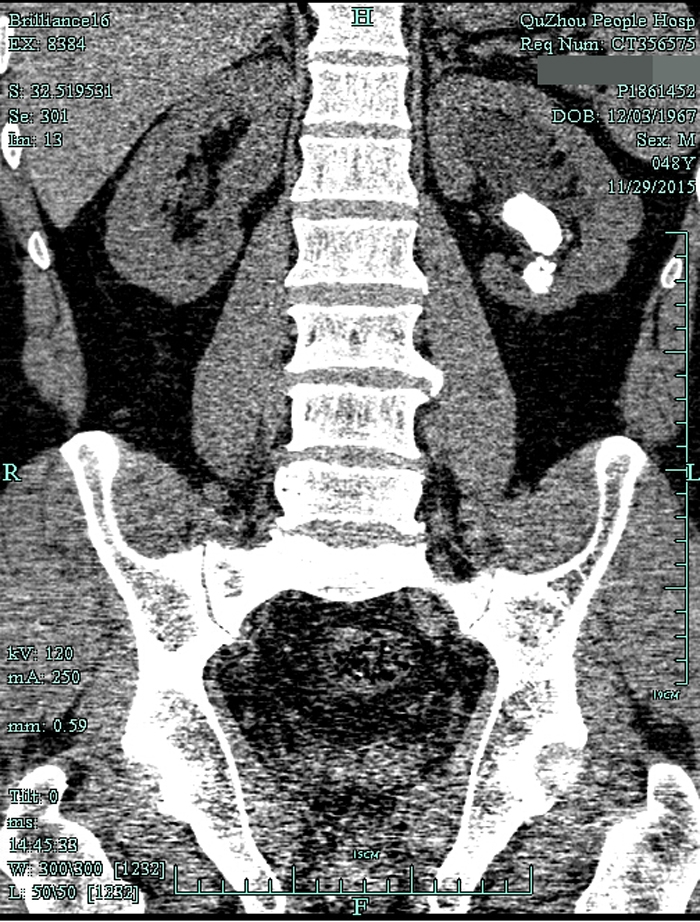

??? 一查泌尿系CT,兄弟倆都是左腎鹿角型結(jié)石,而且已經(jīng)有腎積水。根據(jù)CT檢查結(jié)果以及結(jié)石體積大(3cm)、質(zhì)地硬的特點,萬醫(yī)師建議兩人行經(jīng)皮腎鏡碎石取石術(shù),才能將結(jié)石清理干凈。

術(shù)前CT1

術(shù)前CT2